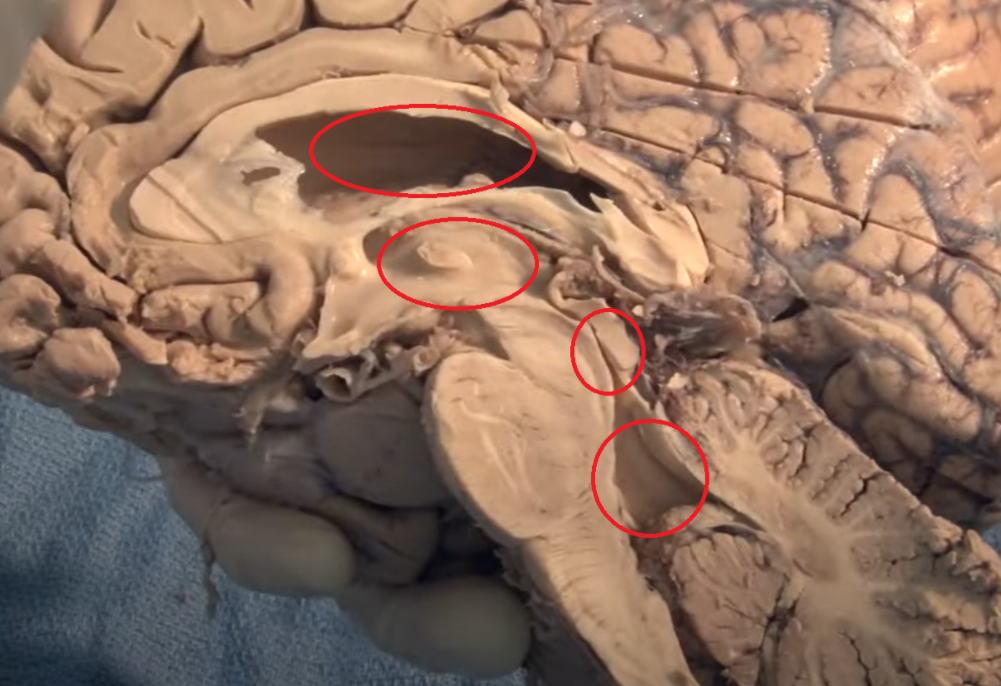

Thalamus (pink) and hypothalamus (yellow): their medial surfaces border the third ventricle (blue).

The purple hippocampus is visualized tracing the ventricular system (turquoise).